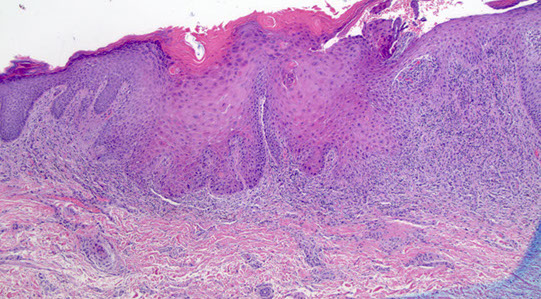

Squamous cell hyperplasia

Micro: can have inc mits, but lacks atypia

aka hyperplastic dystrophy or lichen simplex chronicus

- non-specific rxn to pruritis

- may be present at the borders of malignant lesions